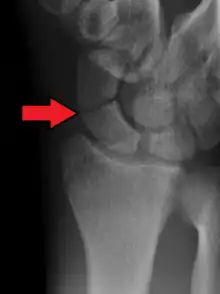

Fracture du scaphoïde

La fracture du scaphoïde est la fracture la plus fréquente du poignet.

A : distale (20% des cas)

B : centrale (60%)

C : proximale (20%).

Le diagnostic de fracture est difficile à réaliser car les lésions éventuelles peuvent ne pas être immédiatement visibles sur les radiographies standard du poignet de face et de profil. On pratique aussi une radiographie avec incidences spéciales (inclinaison de 30° vers le coude) qui permettent de dérouler l'os et ainsi de visualiser plus précisément le trait de fracture[5].